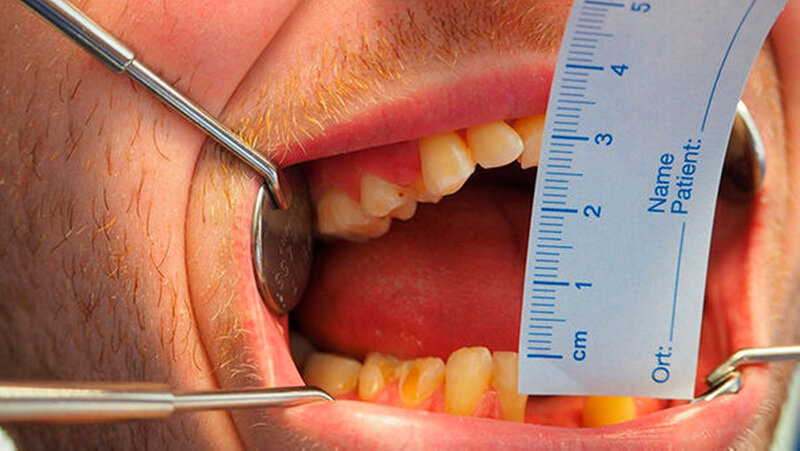

Am zweiten postoperativen Tag begann eine intensive Physiotherapie. Bereits fünf Wochen später betrug die maximale Mundöffnung aktiv 26 mm (Abbildung 11), passiv 32 mm. Nach Stabilisierung einer individuell maximalen Mundöffnung ist die dentale Sanierung geplant, an die bislang situationsbedingt in keiner Weise zu denken war.